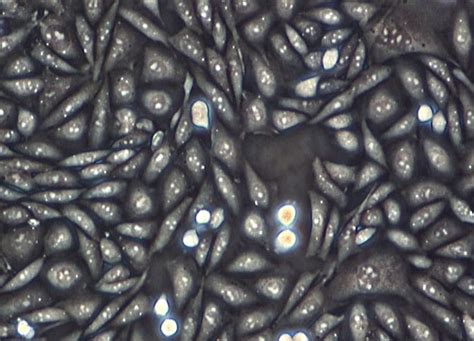

Chinese Hamster Ovary Cell Culture | Nikon’s MicroscopyU

hamster ovary chinese cell culture microscopyu negative.